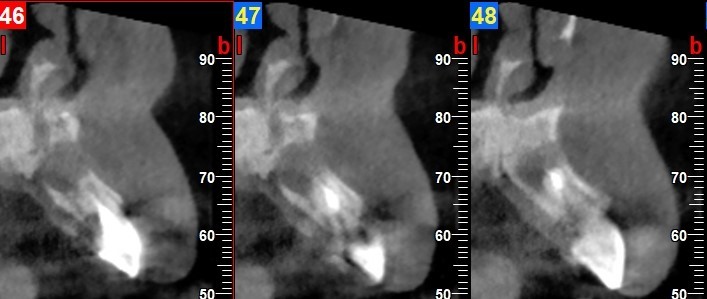

Al test di vitalità gli elementi 21 e 22 risultavano non vitali e all’esame radiografico endorale presentavano un’area di rarefazione periapicale molto estesa (Figura 2).

In accordo con il piano di cura veniva eseguito il trattamento endodontico di 22; dopo circa tre mesi veniva eseguito un ulteriore controllo radiografico che evidenziava una riduzione della lesione periapicale soprattutto a carico del 22 (Figura 3) mentre questa permaneva a carico del 21, per il quale veniva programmata l’estrazione.

Sei mesi dopo, la verifica radiologica CBCT (Figura 7) evidenziava un recupero di radio densità (circa 400 HU) per cui veniva inserito un impianto Biomet-3I Osseotite Tapered Certain di 4 x 13 mm (Figura 8) con torque di inserimento di 20 Ncm.